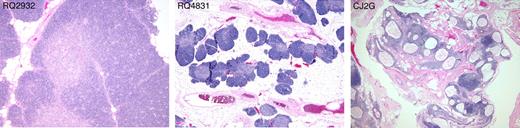

Because KGF primarily enhances epithelial cell growth and thereby may protect TECs, we performed histologic and phenotypic analysis of the thymus 12 to 14 months after transplantation to determine whether preserved thymic architecture might underlie the beneficial reconstitutive effects of KGF treatment described. Slides were analyzed while blinded to the treatment groups and thymic architecture was scored according to 3 grades (Figure 5 and Figure S2). Grade 1 thymi had completely intact architecture with preserved lobular structures and well-defined cortical and medullary areas with high cellularity. Six animals were scored at this grade. One animal (RQ4715) had received multiple doses of KGF and the others (RQ3602, RQ2932, CJ2T, RQ2614) had received a single dose. In addition, one control animal (RQ3576) showed thymic structure of this grade. Grade 2 thymi had areas of well-preserved architecture and high cellularity but with some degree of thymic atrophy in other areas. One animal that received multiple doses of KGF (RQ4831) and one untreated animal (CJ5D) exhibited thymi of this type. Grade 3 thymi showed severe thymic atrophy, defined by fat replacement, decreased cortical thickness, cystic changes of the epithelium, and low cellularity. All 3 remaining control animals belonged to this group. In summary, all 6 KGF-treated animals had no or little thymic atrophy, whereas 3 of 5 control animals had severe thymic atrophy. The weight of the thymi at autopsy did not correlate with the quality of the thymic architecture (Table 1). In addition, a Fisher exact test on the association between KGF exposure (yes/no) and thymus grade (1, 2, or 3) gave a P of .04, suggesting that the preservation of thymic architecture correlated with KGF treatment.

Thymic histology. Hemotoxylin and eosin stains of the thymus of 3 representative animals at necropsy 12 to 14 months after transplantation. Thymus (left panel) scored as grade 1: well-preserved architecture with well-defined cortex and medulla, no atrophic changes. Grade 2 thymus (middle panel): some degree of atrophic changes consisting of fat replacement of lobules and preservation of cortex and medulla and islets of cell-dense tissue containing many thymocytes. Grade 3 thymus (right panel): marked atrophic changes and cystic degeneration. All photos were taken with an Olympus BX41 microscope, objective 4 × /0.13 UPlanFl.